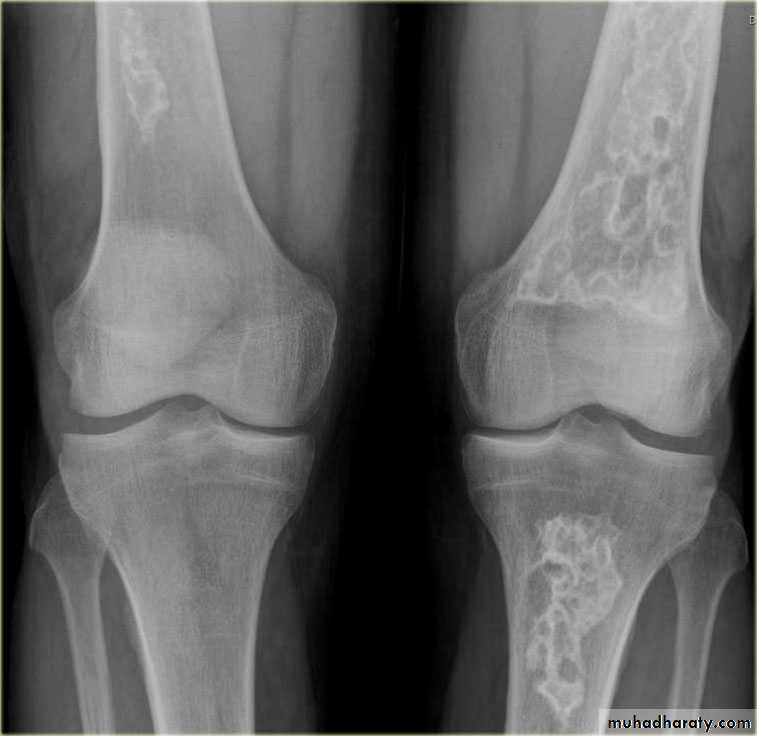

Metastases :Metastases are by far the commonest malignant bone tumor.

Metastases may be sclerotic , lytic or a mixture of lysis& sclerosis

Lytic metastases.

Lytic metastases give rise to well defined or ill defined areas of bone destruction with out a sclerotic rim .the lesions vary from small holes to large areas of bone destruction.

Sclerotic metastases appear as ill-defined areas of increased density of varying size with ill-defined margins .

Mixed lytic & sclerotic metastases are not uncommon , they are often seen with carcinoma of beast .

A radionuclide bone scan is much more sensitive for detecting metastases than plain film .